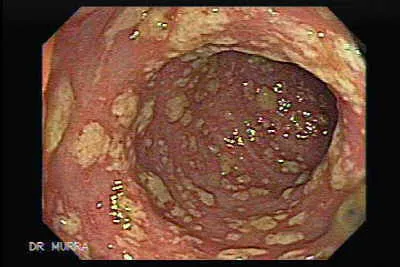

- Causes pseudomembranous colitis (diarrhea, fever, abdominal pain).